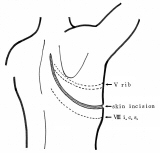

横隔膜切除後広背筋による再建

昔々、胸部外科の先生に頼まれて、描きました。